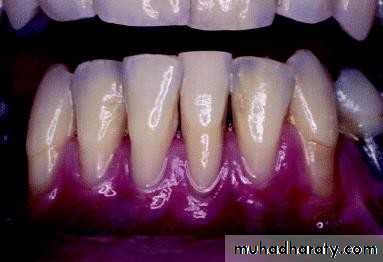

• Periodontal Examination Plaque Control Record

• Disclosing tablets

• Disclosed plaque• Periodontal Examination

• Plaque Control Record

• Factors that hinder patient’s plaque control:

• Calculus.• Poor restoration margins. Over-contoured restorations. Removable partial appliances.